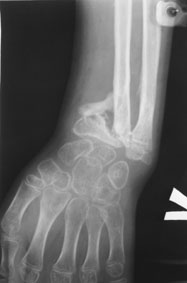

Лучевая косорукость

11-летний любитель лазить по деревьям 7 месяцев назад получил открытый дистальный остеоэпифизеолиз левого луча. ПХО была сделана с трудом; о репозиции, со слов, и не помышляли. Неделю назад удалось открыто адаптировать костные фрагменты, фиксировать аппаратом. Сразу сделали кортикотомию в/3 луча. Начали его удлинение. Вопрос: учитывая отсутствие дистальной зоны роста стоит ли "переудлинить" луч? Если да, то на какую величину?

как видно из Р снимков, дистальная ростковая зона повреждена. делать эпифизеодез думаю что не целесообразно. лучелоктевая косорукость преопределена, поэтому востановление придеться делать в несколько этапов. величину гиперкоррекции предусмотреть трудно не зная темпов роста, думаю что впределах 5-10мм. С уважекнием Владимир Старостенко. купянск .Харьковской. Украина

Глядя на предложенные снимки, сразу же возникает вопрос о необходимости открытого сопоставления отломков лучевой кости. Мне кажется, репозицию возможно было бы сделать и ваппарате Илизарова с использованием смещенных шарниров и этапной дистракции без выполнения разреза. Росковый хрящ, скорее всего, большей частью погиб. Но в аппарате Вы могли срепонировать и стабилизировать отломки, восстановить на время соотношение лучевой и локтевой костей в лучезапястном суставе, пусть даже дозированной осевой дистракцией.

Маленькое замечание: кортикотомия произведена (кажется так по снимку) в невыгодном с точки зрения кровоснабжения кости месте. Дитракция в аппарате приведет к сдавлению не растянутого в аппарате лучезапястного и межзапястного суставов (спица за пястные кости не проведена).